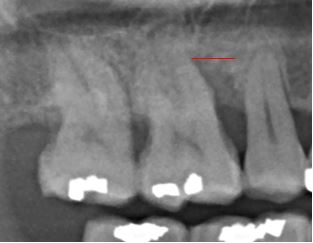

Bone loss is a destructive process that is bacterial-driven and can be exacerbated by clenching and grinding. Using our laser for non-invasive surgical treatment, there has been a significant increase in bone level and attachment around this molar. Patients prefer this surgical treatment because it requires no cutting or sewing of the gum tissue and new bone can be formed. If you struggle with periodontal disease come to see how we can help you get a healthier smile! Visit our webpage at www.frederickimplant.com or give us a call at 240-651-5478 to schedule a consultation.